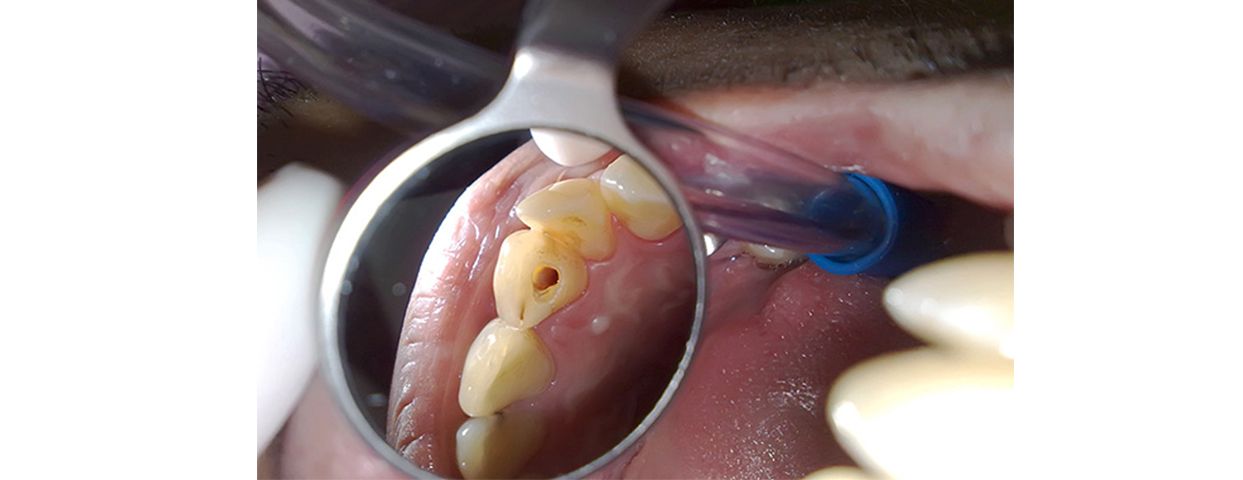

Если острый периодонтит не лечится, он может перейти в хроническую форму, которая характеризуется менее выраженными симптомами, но представляет собой не меньшую опасность․ К хроническим осложнениям относятся хронический периостит, гранулемы, кисты и периодонтиты с формированием свищей․

Хронические осложнения могут протекать бессимптомно в течение длительного времени, постепенно разрушая костную ткань челюсти и приводя к потере зуба․ Поэтому регулярные профилактические осмотры у стоматолога крайне важны для раннего выявления и лечения хронических форм периодонтита․